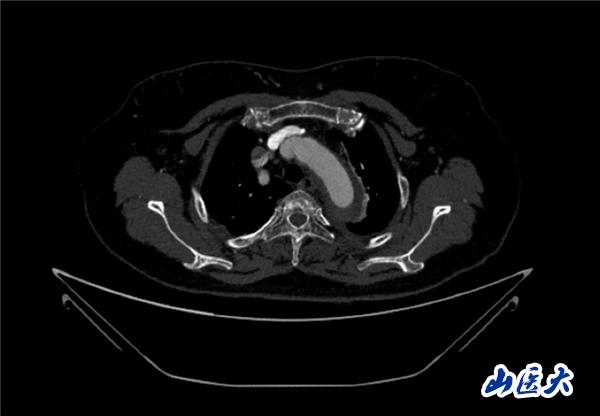

首例患者是一位55歲的女性,她患有高血壓約2年時間,平時也會規律服用多種降壓藥,但血壓控制始終不盡人意。2023年4月下午,她出現不明原因的頭痛,在家拔罐緩解少許便未到醫院就醫,次日凌晨突感胸悶、胸背疼痛伴有呼吸困難等癥狀、家人急忙撥打了120,把患者送入醫院急診科進行救治,醫生在急診科行胸腹主動脈CTA時,顯示主動脈弓部-降主動脈及腹主動脈壁間血腫,遂收治入醫院血管外科,患者入院10天后復查血腫仍未有改善,依然伴有胸背部疼痛等不適,如不進一步處理,可能發展為夾層危及生命,患者及家屬經過與醫生團隊了解溝通,決定進行創傷小、恢復快的介入手術治療。張瑋教授、符偉國教授、董紅霖教授及其血管外科團隊(閆盛、常文凱、田琴琴)共同商討手術方案,最終確定使用Zipper?一體式主動脈弓覆膜支架系統,行胸主動脈覆膜支架腔內隔絕術+無名動脈、左頸總動脈、左鎖骨下動脈分支重建術為患者進行治療。董紅霖教授及其血管外科團隊根據患者術前頭顱CT平掃提示雙側側腦室旁缺血灶,血壓控制不穩定,屬夾層壁間血腫非典型夾層等風險點,制定了完整的手術方案,術中經股動脈置入Zipper支架主體,經預留導絲超選無名動脈,并確保主體支架對位準確,順利置入左頸總動脈、左鎖骨下動脈支架,重建弓上三分支。手術過程非常順利。術后觀察主動脈及分支覆膜支架定位準確;無內漏;分支支架通暢,動脈供血正常。

術前CTA